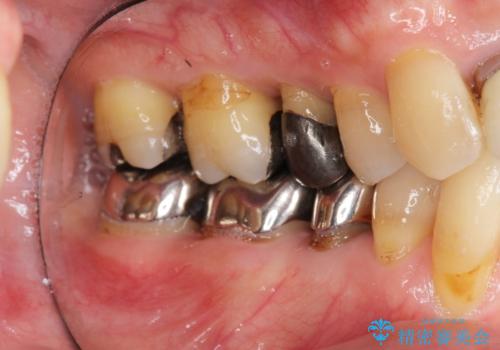

- 前歯の見た目・歯並び・銀歯の見た目の改善を求めて来院されました。

まずガタ付きの強い歯並びをマウスピース矯正インビザラインで整えたのち、セラミック治療による審美性の改善を計画します。

矯正治療が終わったのちに、精度の高いセラミックを装着することでより安定した噛み合わせとなり審美性も兼ね備えた口腔内状態で治療を終了し、今後のメンテナンスを行っていくことができます。